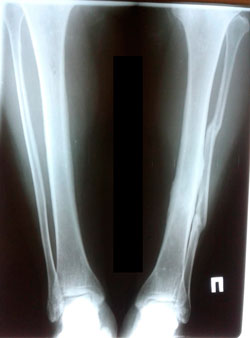

Исходник - 46 лет.

Дата операции - 01.10.2020

image-30-09-20-06-09-2.jpg

image-30-09-20-06-09-1.jpg